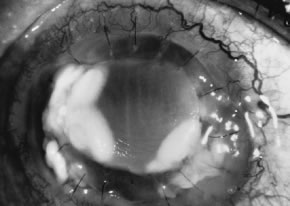

There is no distinguishing clinical sign by which to recognize the genus or species of the infectious filamentous fungus. F. solani is the most virulent organism and typically produces rapidly progressive infection characterized by epithelial and stromal ulceration, dense stromal necrosis, abundant cellular infiltrate, and edema in the adjacent stroma and hypopyon (Figs. 8 and 9). Delicate feathery components are transient. Individual hyphal fragments are rarely visualized. Infection by certain species of Aspergillus and Scedosporium (Figs. 10 and 11) resembles F. solani keratitis and progresses rapidly. Infection by less virulent organisms, such as Curvularia and Alternaria species, produces small, focal (less than 3-mm diameter) areas of nonnecrotizing stromal inflammation with delicate feathery borders (see Fig. 1 and Fig. 12). Macroscopic pigmentation may develop in keratitis caused by Alternaria, Curvularia, and other dematiaceous fungi (Fig. 13).4,11,14 The central component may progress to dense, opaque, gray-white suppuration in the deep stroma without enlargement in total area and may be accompanied by mild inflammation in the adjacent stroma. Iritis is minimal to moderate. Infection caused by other, relatively less virulent organisms resembles herpes simplex or noninfectious keratitis (Fig. 14).

Fig. 8. F. solani keratitis. Note the dense opaque central necrosis surrounded by fluffy, nonhomogeneous infiltrate.

Fig. 9. F. solani keratitis. Epithelial and stromal ulceration and necrotizing stromal keratitis.